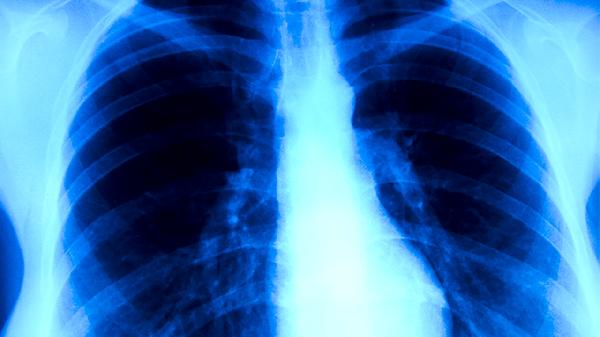

肺结核传染性主要通过飞沫传播,当患者开始规范服用异烟肼片、利福平胶囊、吡嗪酰胺片等抗结核药物后,病原菌活性会快速被抑制。早期规律用药1-2周内,患者咳嗽咳痰症状明显减轻,痰液中结核分枝杆菌数量显著下降。持续用药至2-3周时,多数患者痰涂片转阴,此时传播风险已大幅降低。但部分重症患者或存在耐药菌株时,可能需要更长时间才能达到非传染状态。治疗期间需定期进行痰菌检查,医生会根据微生物学检测结果评估传染性变化。即便症状消失后,患者仍需完成6-9个月的标准疗程以彻底杀灭休眠菌,避免复发和继发性耐药。